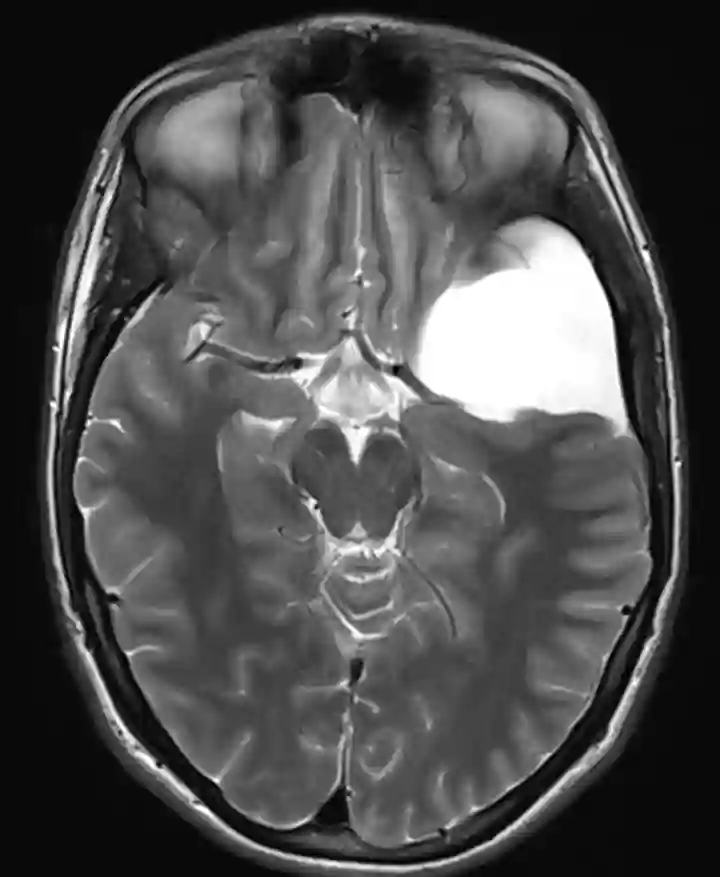

Bildgebung

Arachnoidalzysten können in der CT als auch MRT Bildgebung visualisiert werden.

Arachnoidalzyste im MRI.

Axiale T2 Sequenz im MRI eines Patienten mit einer Galassi Typ 2 Arachnoidalzyste.